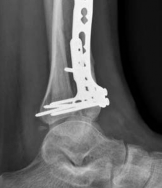

Image

Digital templating is utilized to select the appropriate implant. For a fracture extending into the diaphysis, an extra-long anatomical distal tibia locking plate is required. The surgeon must determine whether an anterolateral or medial plate (or dual plating) will provide the optimal biomechanical construct based on the fracture morphology. The trajectory of the distal locking screws must be planned to provide a subchondral raft supporting the articular surface without penetrating the joint space. Furthermore, the availability of bone graft or orthobiologics must be confirmed, as elevating impacted articular segments will leave a metaphyseal void requiring structural support.

With the articular surface reconstituted, the surgeon's focus shifts to bridging the complex metaphyseal-diaphyseal dissociation. A pre-contoured anatomical locking plate is slid submuscularly or subcutaneously along the diaphysis using a MIPPO technique. The plate is positioned on the anterolateral or medial surface, depending on the preoperative plan and soft tissue constraints.

The distal portion of the plate is secured to the reconstructed articular block. It is imperative that the distal locking screws are placed parallel to the joint space, forming a rigid subchondral raft that supports the articular cartilage. Fluoroscopy is utilized extensively to ensure no screws have penetrated the joint. Once the distal block is secured to the plate, the diaphyseal segment is aligned. Length, alignment, and rotation are restored using manual traction or the femoral distractor. The proximal portion of the plate is then secured to the diaphysis using a combination of non-locking screws (to pull the bone to the plate) and locking screws (to create a fixed-angle construct). The working length of the plate is maximized by leaving several screw holes empty over the zone of comminution, promoting secondary bone healing.